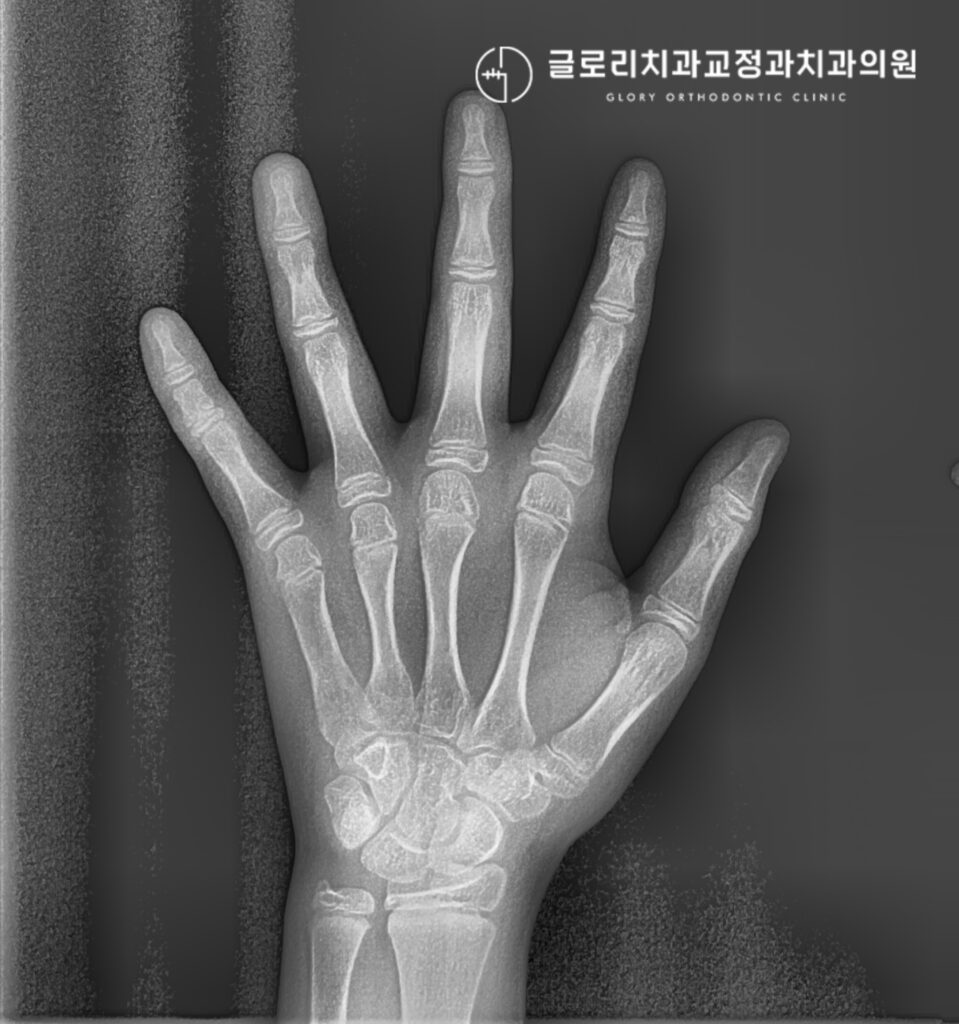

보다 정밀한 진단을 위해 수완부 방사선 사진을 기준으로 평가한 발달단계에서 11단계중 4-5단계로 성장 개시기를 지나 가속기 단계로 평가됩니다.

이 시기는 사춘기 성장 급증기에 해당하여 하악골의 잠재력이 활발하게 발현되는 구간이기도 한데요.

기능성 교정장치를 통한 성장 조절치료의 효과를 크게 기대할 수 있는 골든타임이라 할 수 있습니다.